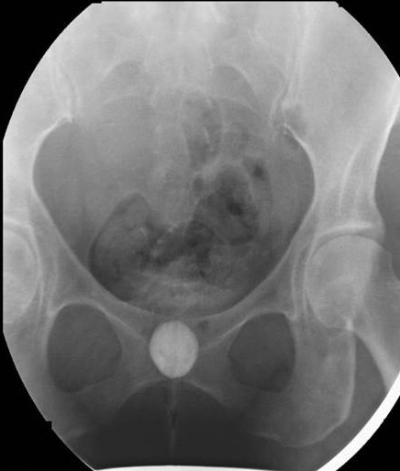

Figure 1b: Supine image showing urethral diverticulum.

Figure 1 shows a well defined rounded area filled with contrast that remains after bladder emptying. Note the small filling defect on the right side of the diverticulum (arrow), in keeping with a tumour. Double-balloon urethrography can also be used, despite having a greater sensitivity than voiding cystourethrography [2] it is more technically difficult. More recently, cross-sectional imaging has become more popular due to the greater need to delineate the diverticula and investigate malignant transformation [4].